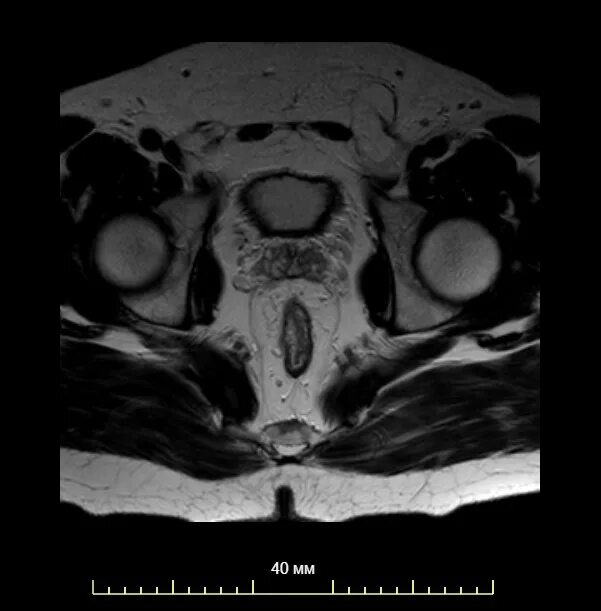

Где можно сделать кт малого таза